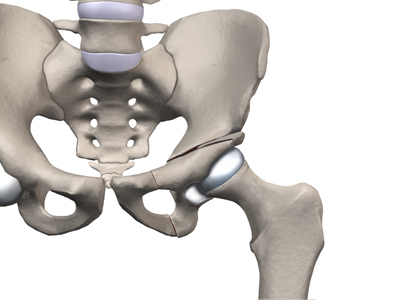

Surgical treatment for containment usually consists of procedures that realign the femur (thighbone), the acetabulum (hip socket), or both.

Realignment of the femur is called a femoral osteotomy. This procedure changes the angle of the femoral neck so that the femoral head points more towards the socket. To perform this procedure, an incision is made in the side of the thigh. The bone of the femur is cut and realigned in a new position. A large metal plate and screws are then inserted to hold the bones in the new position until the bone has healed. The plate and screws may need to be removed once the bone has healed.

Realignment of the acetabulum is called a pelvic osteotomy. This procedure changes the angle of the acetabulum (socket) so that it better covers, or contains, the femoral head. To perform this procedure, an incision is made in the side of the buttock. The bone of the pelvis is cut and realigned in a new position. Large metal pins or screws are then inserted to hold the bones in the new position until the bone has healed. The pins usually must be removed once the bone has healed.

In severe cases, both femoral osteotomy and pelvic osteotomy may be combined to obtain even more containment.